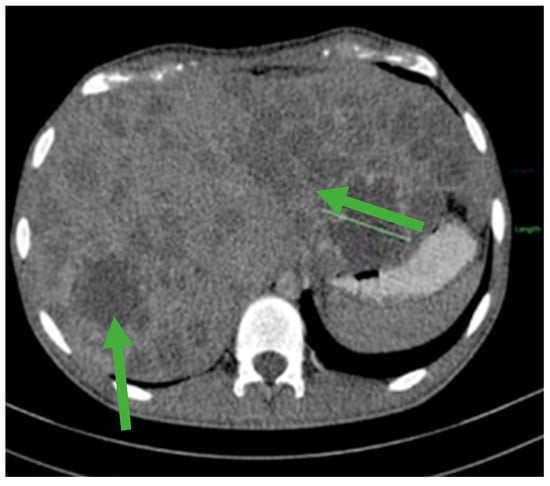

Figure 3.

Hepatomegaly and multiple liver metastases (green arrows).

Figure 4.

CT scan showing liver metastases in numerical and dimensional progression (green arrows).